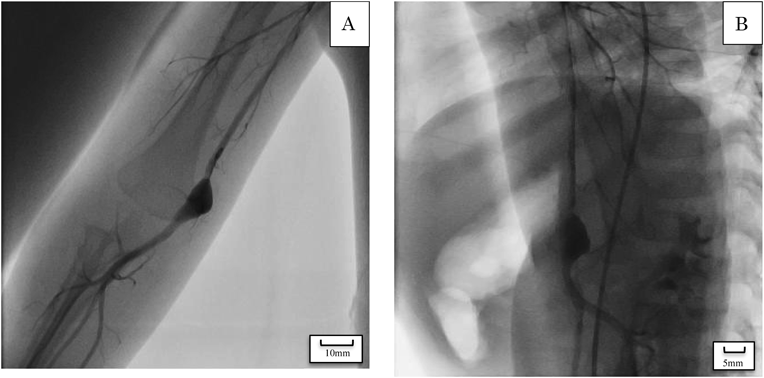

Fig. 3 Angiographic imaging of the aneurysm

Angiography demonstrates a single brachial artery aneurysm, seen here in frontal view (A) and lateral view (B). The irregularity of the posterior wall is suggestive of clots and mild stenosis of the artery on the proximal side of the aneurysm.